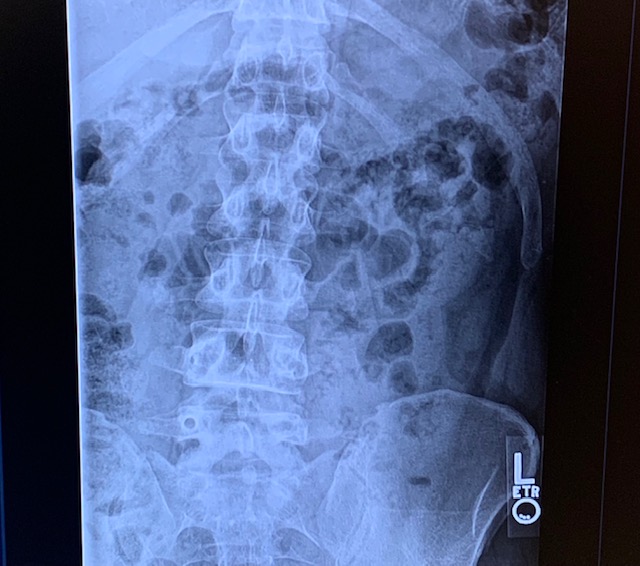

I came to HSS Stamford with broken hardware from a failed spinal fusion with another hospital. I was very reluctant as I wasn’t having good experiences elsewhere for my pain. Dr. Evan Sheha went over my imaging and took more time speaking with me than my previous three doctors combined. He listened. From my complaints, Dr. Sheha followed up with injections to make sure a hardware removal would actually help. It did!